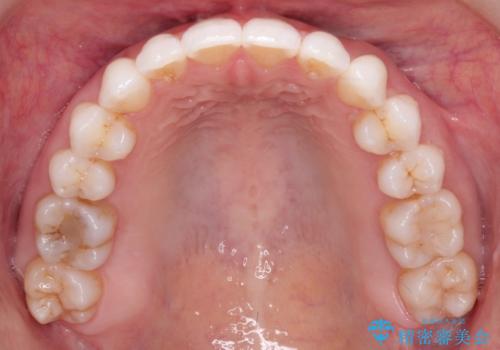

インビザライン中のホワイトニングについて

基本的に矯正中であってもホワイトニング自体は施術可能です。

マウスピース矯正用のマウスピースは、ご自宅で行うホームホワイトニング用のトレーとしてご利用いただくことができます。

※インビザライン治療の場合ホワイトニングを行う前歯にアタッチメントと呼ばれるポッチを歯の表面に付けることがあるため、アタッチメントがついた状態でホワイトニングを行うことはオススメしておりません。